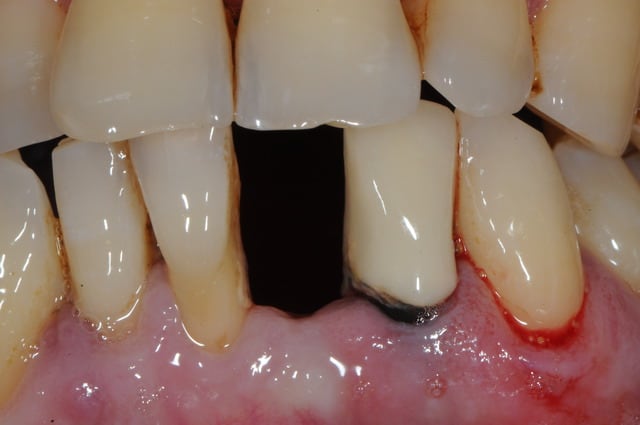

et ici ?? vous feriez quoi ?

32 et 42 pas mobiles

malheureusement, l'espace est réduit pour mettre deux implants.

comment avez vous déjà géré ce type de cas ??

le haut est déjà traité...